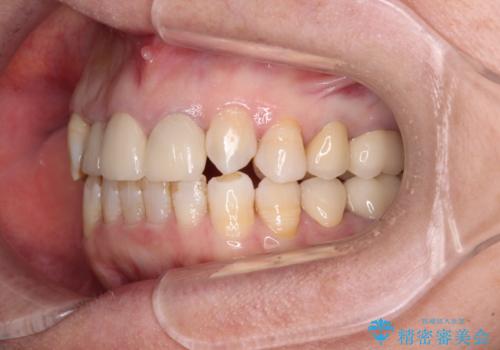

歯冠長延長術を行ったことで、自然な形態かつ清掃性の高いセラミッククラウンを装着することができました。

全顎的に治療を行ったため、治療期間も費用も負担は大きくなりましたが、統一感のある仕上がりとなりました。